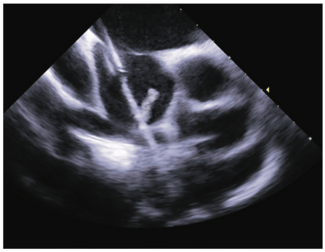

Herein, we report the case of a female patient who underwent transcatheter closure of an atrial septal defect with the use of an Amplatzer Septal Occluder (Abbott Vascular) under intracardiac echocardiography guidance where acute thrombus...